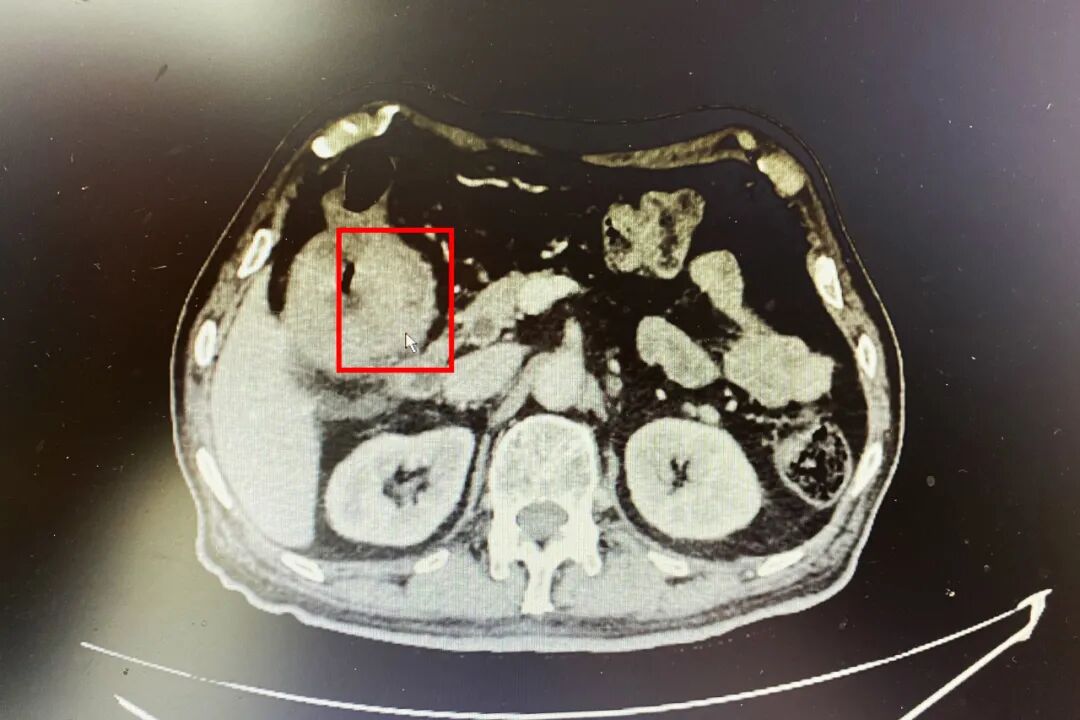

直到不小心摔了一跤,在当地医院做检查,竟意外发现他肚子里有个成人拳头大的“包块”。

最终诊断为右半结肠肿瘤,合并肠梗阻。

如不及时治疗,肿瘤将继续生长,最快一两个月就会完全堵住肠道,出现完全性肠梗阻,危及生命。